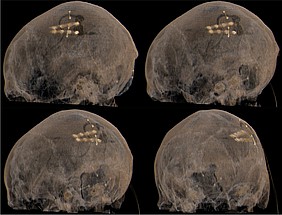

Bei bestimmten Bewegungsstörungen, die nicht oder nicht mehr ausreichend auf eine medikamentöse Therapie ansprechen, ist es möglich, die hierfür verantwortlichen Hirnareale durch die sog. Tiefe Hirnstimulation zu beeinflussen. Hierbei werden feine Elektroden in das Gehirn eingesetzt, um fehlerhafte Nervenstrukturen mit elektrischen Impulsen zu aktivieren oder zu hemmen. Beim Morbus Parkinson, dem essentiellen Tremor oder der Dystonie sind beispielsweise spezifische Hirnareale überaktiv, die dann gezielt durch die Tiefe Hirnstimulation gehemmt und die Symptome wie Zittern oder Muskelsteifigkeit dadurch unterdrückt werden können. Die Hirnregionen selbst bleiben dabei intakt, sodass die Stimulation jederzeit rückgängig gemacht werden kann. Die elektrische Stimulation wird durch einen Impulsgeber gesteuert, der ähnlich wie ein Herzschrittmacher unter die Haut an der Brust der Patient:innen implantiert wird. Die Einstellungen des Impulsgebers lassen sich von außen jederzeit verstellen, sodass die Stimulation an veränderte Bedürfnisse der Patient:innen stets angepasst werden kann.

Bei der transkraniellen fokalen Kortexstimuation wird eine dünne Elektrode unter die Haut auf den Schädelknochen gelegt.

Bei beiden Verfahren wird die elektrische Stimulation durch einen Impulsgeber gesteuert, der ähnlich wie ein Herzschrittmacher unter die Haut an der Brust der Patient:innen implantiert wird. Die Einstellungen des Impulsgebers lassen sich von außen jederzeit verstellen, sodass die Stimulation an veränderte Bedürfnisse der Patient:innen stets angepasst werden kann.